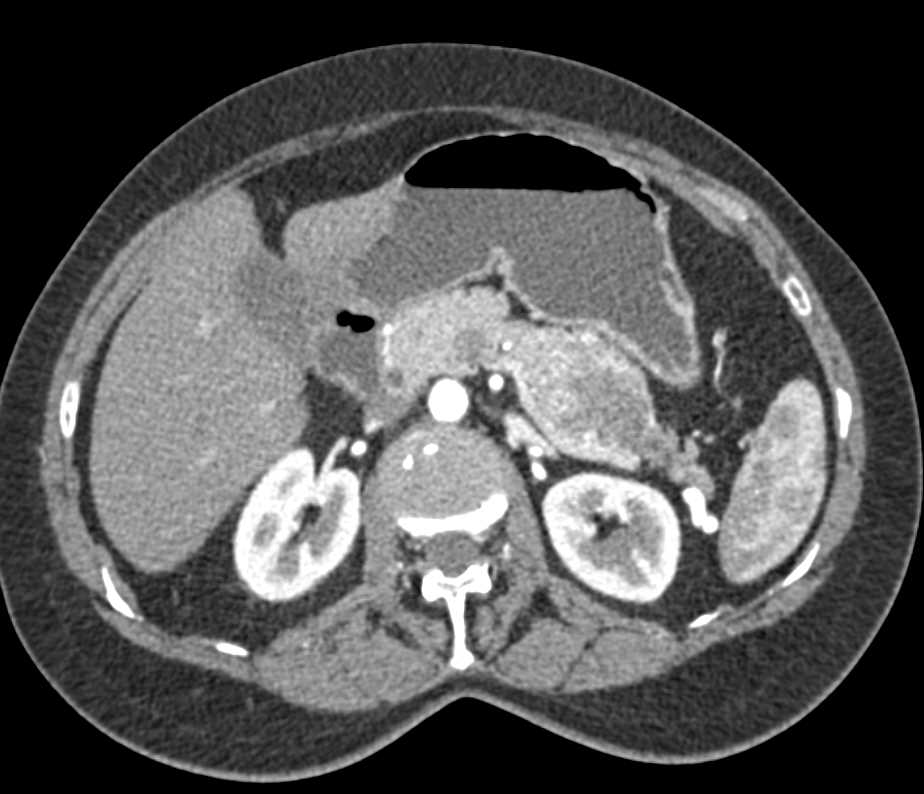

Gastric GIST Tumor Abuts the Pancreas